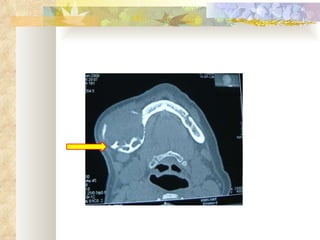

INVESTIGATIONS Radiological – OPG, lateral occlusal mandibular radiograph Complete blood picture, CT, BT Incisional biopsy

Bicortical expansion

RADIOLOGICAL FEATURES Unilocular radiolucency, especially early lesions that often progress to multilocular ( soap-bubble, honeycomb ) May be associated with impacted tooth Cortical expansion and thinning Resorption of adjacent tooth roots, displacement of teeth can be seen